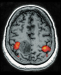

Functional Magnetic Resonance Imaging (fMRI) in Brain Tumour Patients European Association of NeuroOncology Magazine 2012; 2 (3): 123-128 PDF Summary Figures Keywords: brain mapping, brain neoplasms, functional, glioma, magnetic resonance imaging, motor cortex Functional magnetic resonance imaging (fMRI) is increasingly used in the work-up of brain tumour patients preoperatively to assess the relationship between the functionally eloquent cortex and brain pathology. In cases of presumed tumour localisation in or near eloquent brain areas, such as the motor cortex or language areas, fMRI may be advantageous to guide the neurosurgical approach, shorten surgery duration, and obtain prognostic information prior to surgery. For the assessment of the primary motor cortex a good correlation between fMRI and intraoperative electrocortical mapping (ECM) has been reported, with sensitivities and specificities ranging from 88–100 %. For the localisation of language representation areas validation results are controversial with sensitivities from 22–100 % and specificities from 0–100 %, rendering fMRI less suitable as the sole technique for language cortex localisation. For the assessment of hemispheric language lateralisation, however, > 90 % agreement between fMRI and the invasive Wada test has led to fMRI now mostly having replaced the Wada test for this indication. There are several limitations of fMRI including issues that are inherent to the technique such as spatial and geometric uncertainty, tumour effects on the fMRI signal, interand intra-individual variability, lack of discrimination between essential and modulating brain regions, and lack of information on the underlying white matter. Such shortcomings need to explicitly be taken into account in every patient. The careful use of fMRI is justified to aid neurosurgical planning but intraoperative ECM remains the gold standard for localising the eloquent brain cortex. |